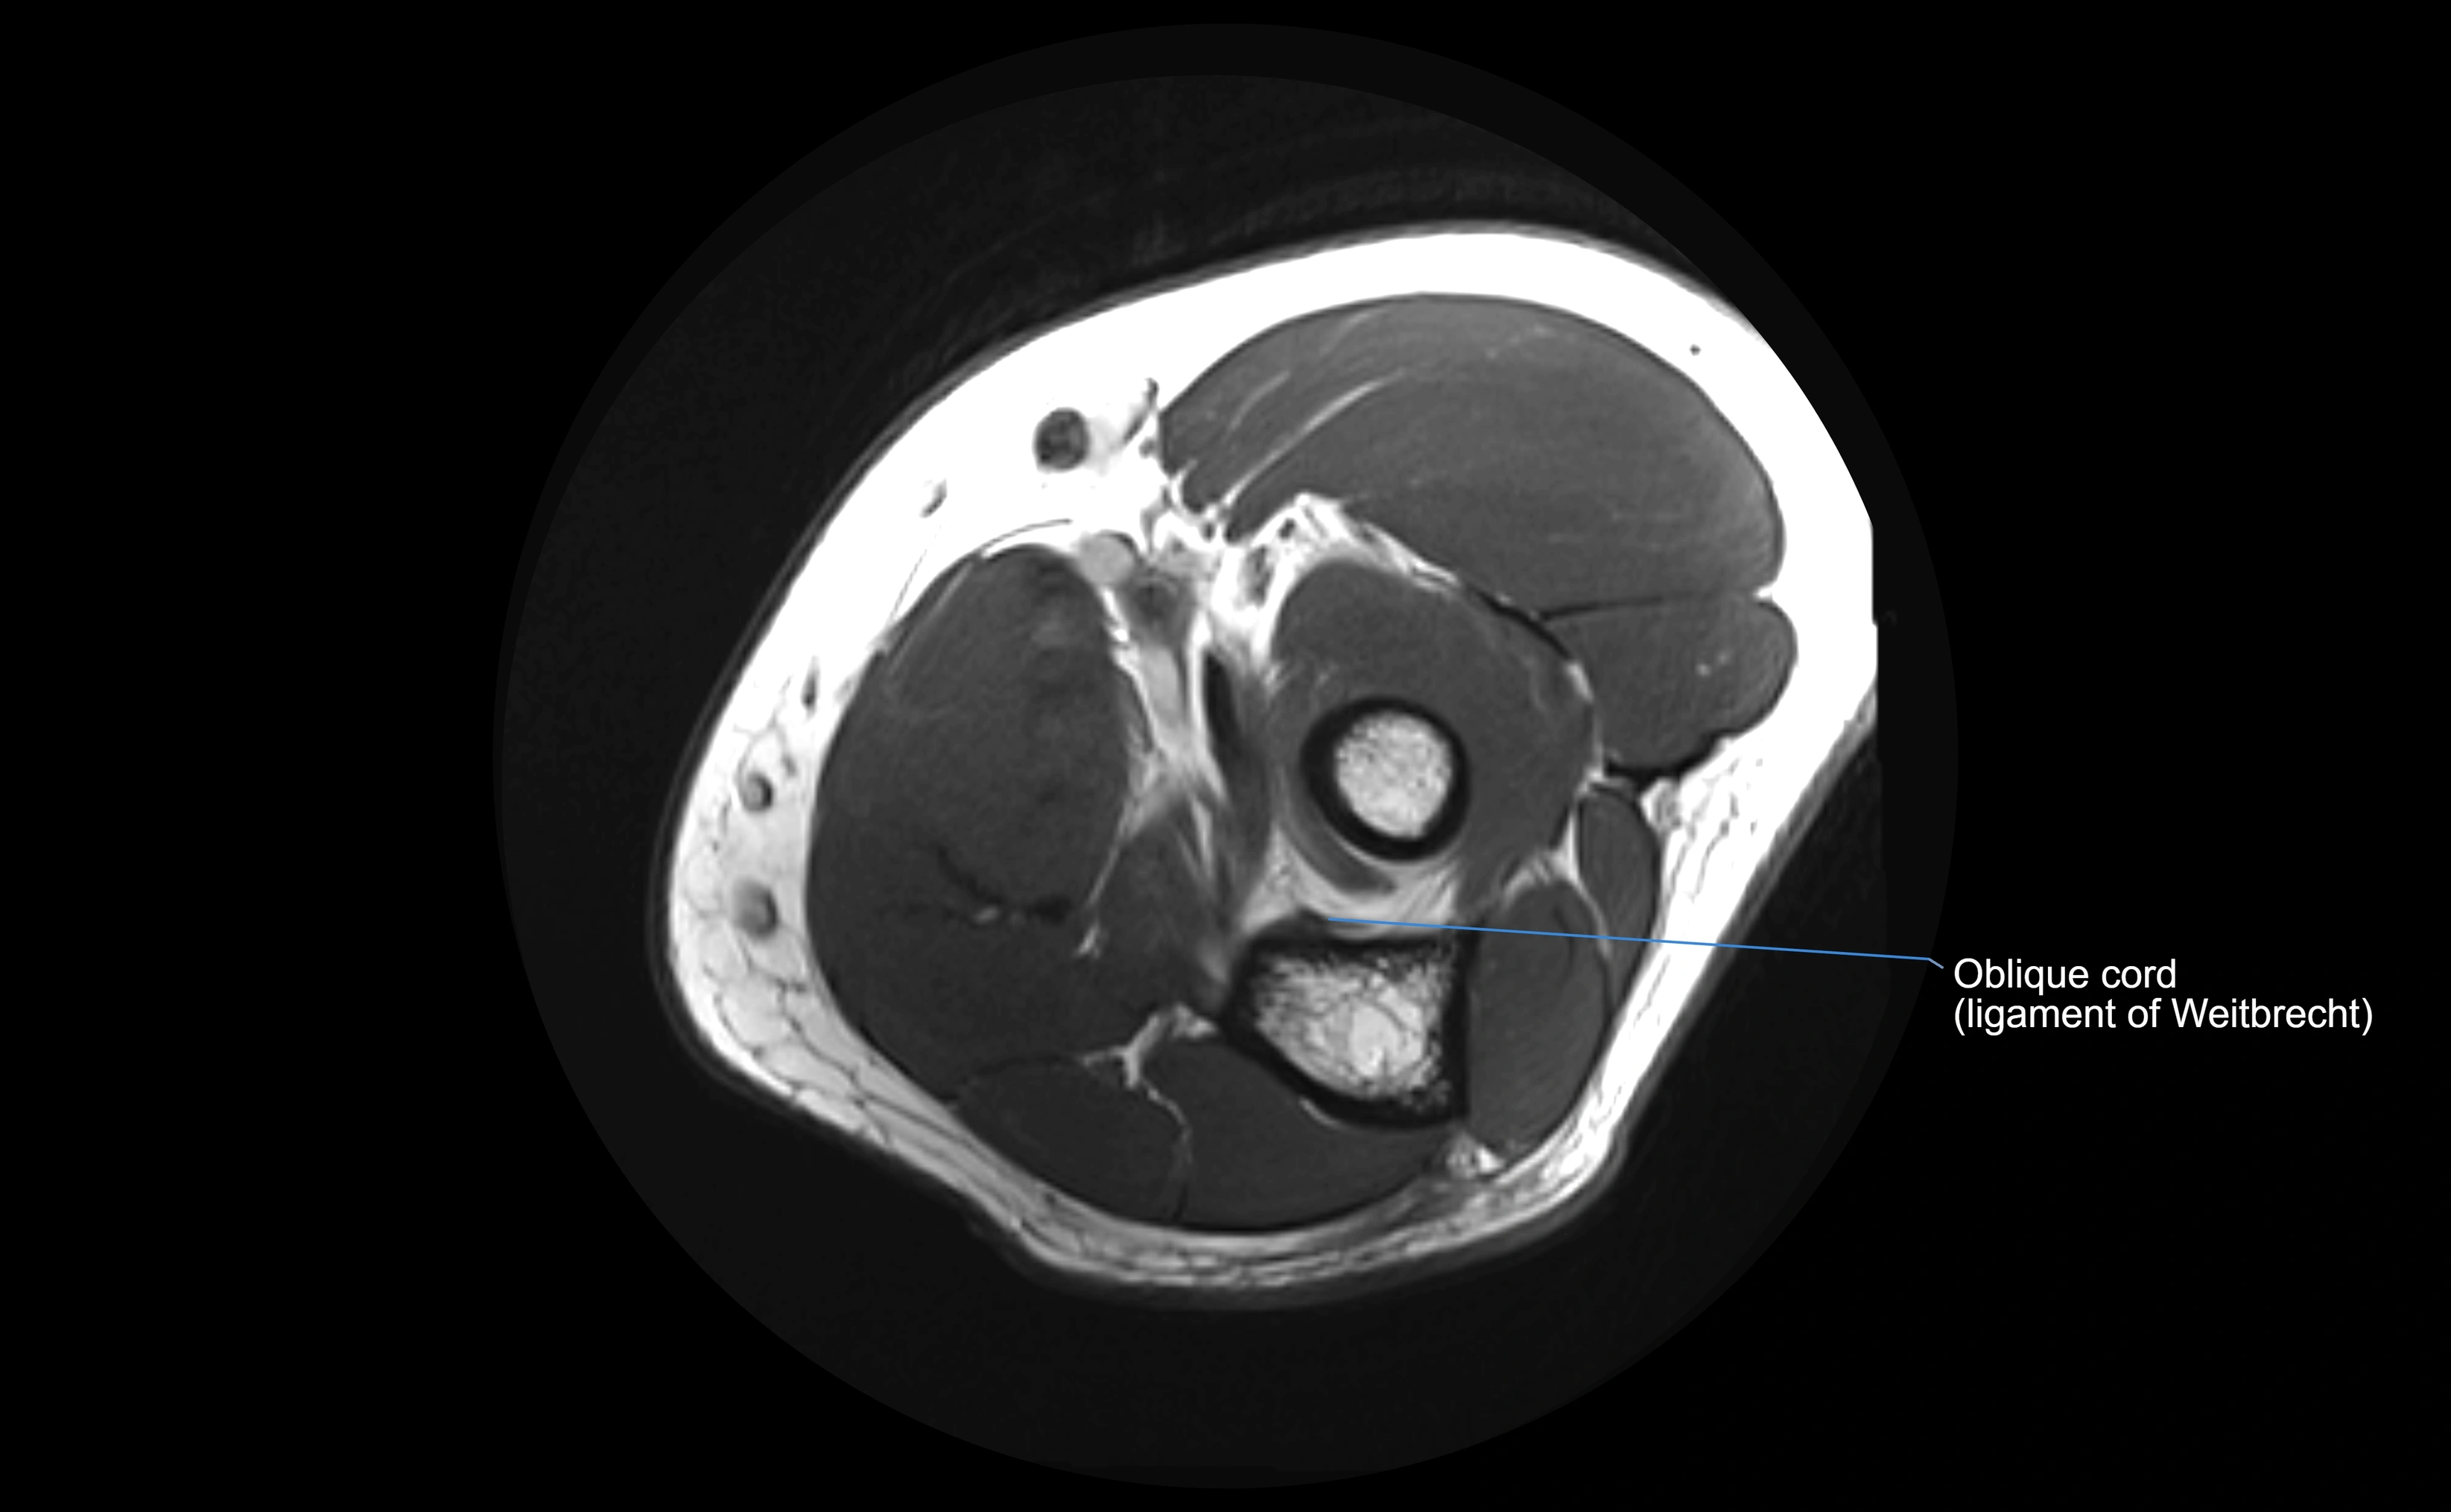

MRI Appearance

STIR:

• Normal ligament: dark band encircling radial head.

• Pathology: bright hyperintense periligamentous signal suggesting edema, sprain, or partial tear.

Proton Density Fat-Saturated (PD FS):

• Normal: dark, well-defined band outlining the radial head.

• Partial tear: irregular or bright hyperintense signal within or adjacent to ligament fibers.

• Joint effusion and reactive synovitis appear bright and are well visualized.

MRI images

image